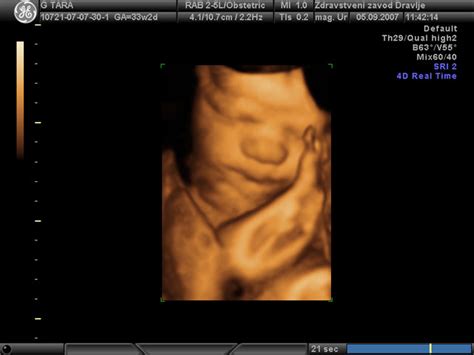

V 19. tednu nosečnosti otrok od temena do trtice meri približno 15,3 cm in tehta okoli 240 gramov. V tem času se razvijajo edinstvene značilnosti, kot so prstni odtisi. Pojavi se zaščitna plast, imenovana verniks, ki obdaja otrokovo telo, živce pa obda mielinska ovojnica, ki omogoča bolj usklajene gibe. Začnejo nastajati stalni zobje.

Otrokovi čutni organi so že dovolj razviti, da otrok kaže reakcije na zvok in dotik. Sliši glasove in jih prepoznava, odziva se na toplino rok, ki jih mati položi na trebuh. Uri sesalni refleks s sesanjem palca, kar mu bo pomagalo pri umirjanju in zagotavljanju hranil po rojstvu.

Glede na spol, če gre za dečka, je mošnja že vidna, čeprav testisa še nista sestopila. Pri deklicah je do 19. tedna v jajčnikih že nastalo več milijonov jajčec.